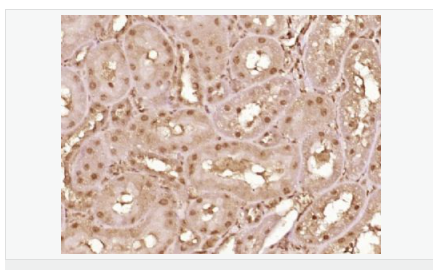

產(chǎn)品應(yīng)用WB=1:500-2000 ELISA=1:5000-10000 IHC-P=1:100-500 IHC-F=1:100-500 IF=1:100-500 (石蠟切片需做抗原修復(fù))

細(xì)胞定位細(xì)胞核 細(xì)胞漿 細(xì)胞膜